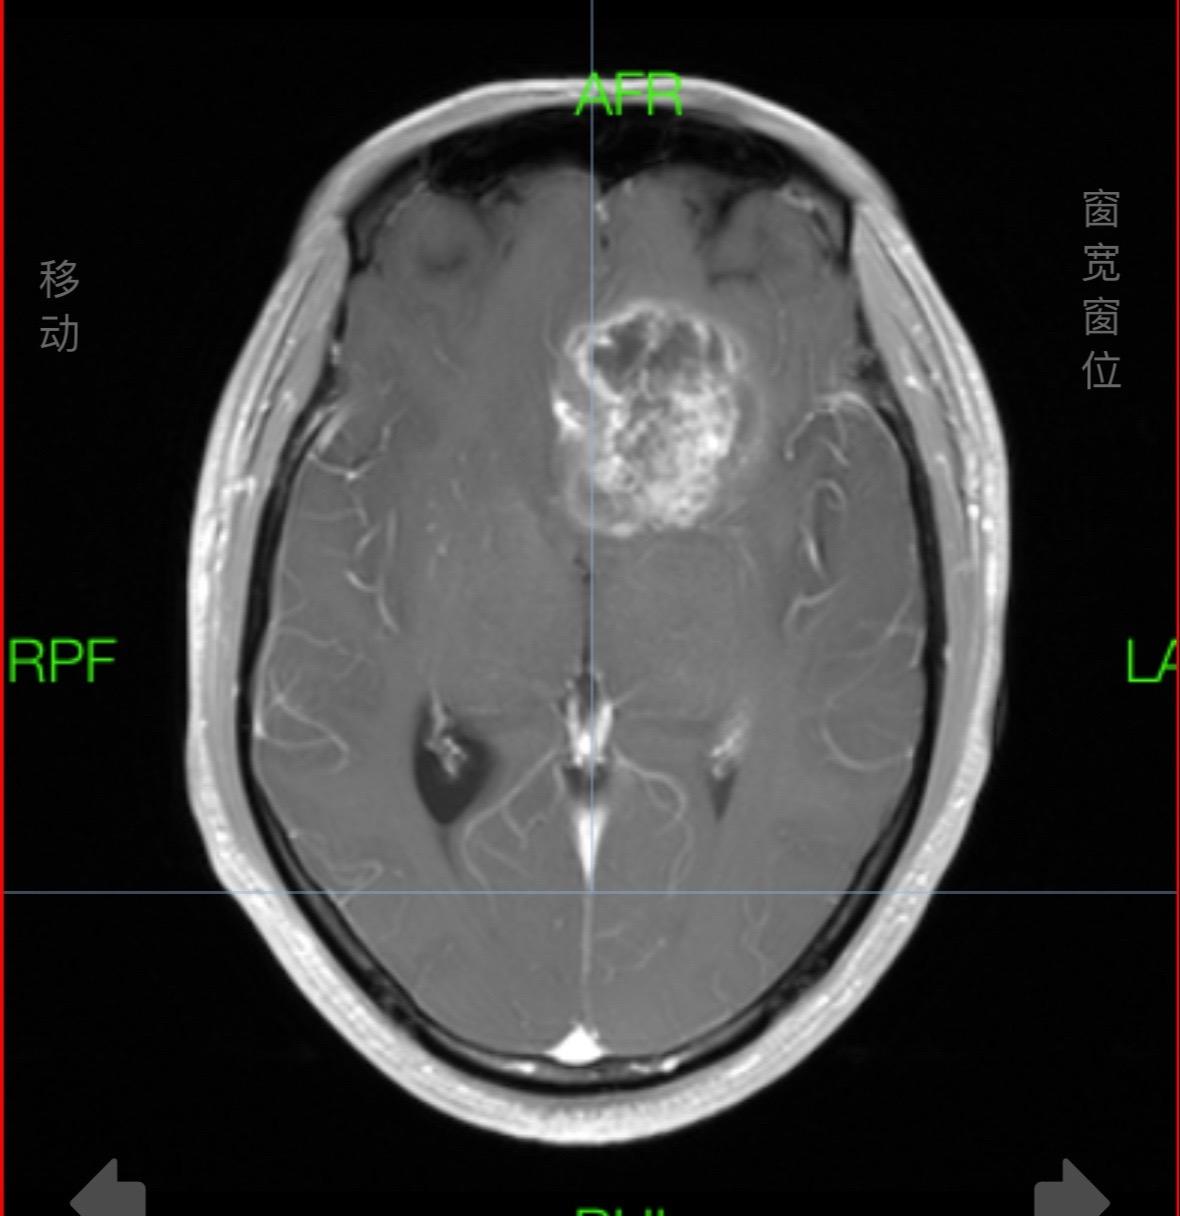

掩盖牙痛的手术。这个肿瘤,周边的重要结构实在太多了,连前交通复合体、内囊前肢、下丘脑、脑室壁、尾状核、中动脉等都一一暴露,如刀尖上行走,手术中导航加持,术中磁共振如同老师一般给你阅卷打分,没想到术中的专注还有意想不到的效果,因为做手术前牙痛,没想到都因为专注做完手术还好了点,看来没入错行,一举两得!